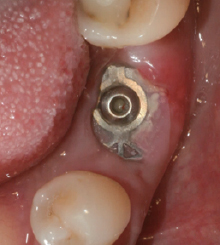

⑤ 3주 치유

⑥ Wifi-Mesh 제거

전, 후 치은 높이보다 1mm 낮게